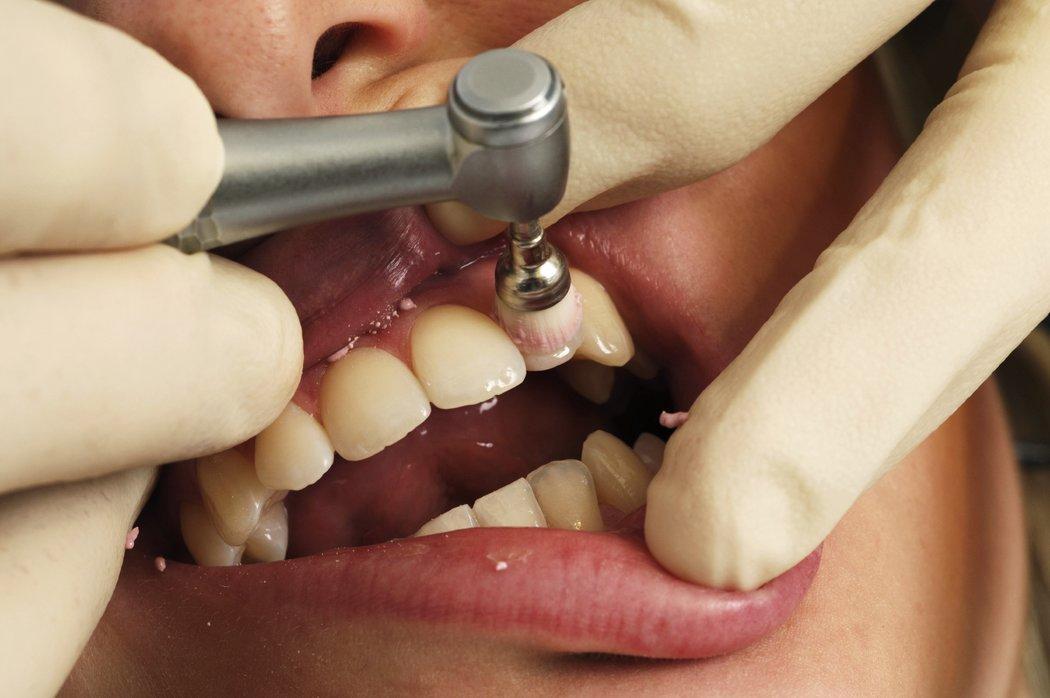

牙龈萎缩很常见,所有人都有可能发生,要记得,发际线可以补,但这宽度仅仅几毫米的粉色黏膜一旦失去就几乎无法恢复。为了预防牙龈萎缩,除了勤漱口、勤刷牙、正确用牙线等日常生活习惯之外,木主任还建议大家,每6~12月洗一次牙,是预防牙龈萎缩的重要措施。